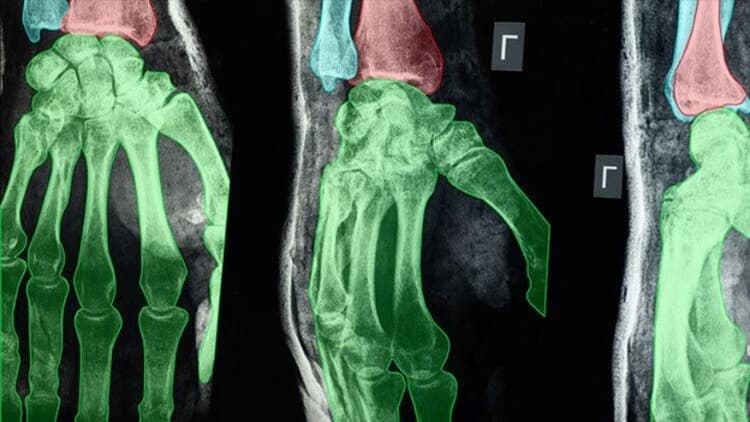

Radiology and Pathology

AI is transforming radiology. It enhances diagnostic accuracy by finding subtle patterns in medical images that the human eye may miss. This capability is crucial for early detection of conditions like neurological disorders, and cardiovascular diseases. For example, AI-enhanced SPECT imaging has been shown to improve the detection of coronary artery disease by generating images similar to those from more expensive hybrid scanners, reducing costs and time, while maintaining accuracy.

AI's real-time image analysis helps make faster, better decisions. This is vital in emergencies.

Moreover, AI systems continuously learn from each scan, becoming increasingly adept at detecting new patterns and emerging health trends. As radiology shifts to data-driven, AI-assisted models, it will see a future of better, faster, and more patient-centered diagnostics.

For instance, collecting high-quality X-ray, CT, and MRI data can be challenging. To overcome this, Keymakr collaborates with a network of local and overseas partners to build custom medical imaging datasets. The team is capable of classifying, validating, and preparing datasets for various medical diagnoses. If a company starts without a defined process, Keymakr can assist in developing a model that suits special requirements. It spans disease detection, surgical AI, pathology research, and other projects.

- Bounding Box: This tool marks areas of interest in medical images, such as identifying tumors in MRI or CT scans, and assists with initial screenings.

- Semantic Segmentation: This tool classifies each pixel in an image to identify specific anatomical structures or conditions, such as separating organs in radiological images. It is crucial for precise surgical planning.

- Keypoint Annotation: Useful for tasks like analyzing joint positions in musculoskeletal images or tracking anatomical landmarks in 3D scans. This tool helps in the assessment of movement disorders or surgical outcomes.